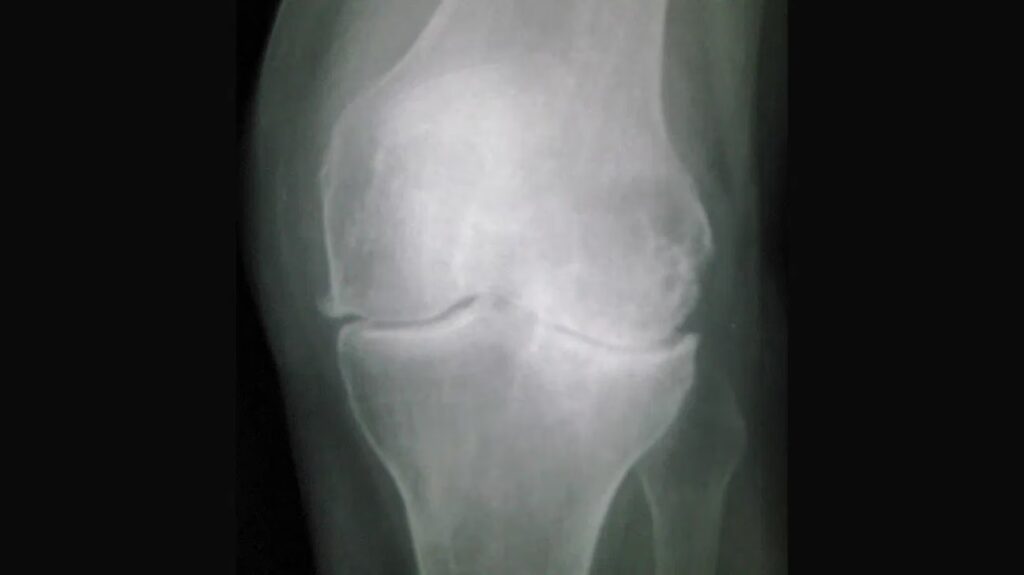

De fire kardinaltegn på knæartrose på et røntgenbillede

Radiologer og ortopædkirurger ser efter fire primære tegn på et røntgenbillede for at diagnosticere og vurdere sværhedsgraden af knæartrose. Disse tegn afspejler de underliggende patologiske forandringer, der sker i leddet, efterhånden som sygdommen udvikler sig.

1. Ledspalteafsmalning

Det mest almindelige og sigende tegn på knæartrose er ledspalteafsmalning. I et sundt knæ er der en tydelig afstand mellem enderne af lårbenet (femur) og skinnebenet (tibia), som er fyldt med ledbrusk. Efterhånden som denne brusk nedbrydes og bliver tyndere, mindskes afstanden, og knoglerne kommer tættere på hinanden. Denne indsnævring er et direkte tegn på brusk-tab og er ofte det første, en læge vil identificere.

2. Osteofytter (Knogleudvækster)

Osteofytter, også kendt som knoglesporer eller knogleudvækster, er et andet klassisk tegn på artrose. Dette er benede fremspring, der udvikler sig langs kanterne af leddet, som kroppens forsøg på at reparere skaden ved at skabe ny knogle. På et røntgenbillede fremstår osteofytter som skarpe, uregelmæssige vækster på kanterne af knæknoglerne, hvilket signalerer, at leddet har gennemgået degenerative forandringer.

3. Subkondral sklerose

Subkondral sklerose er en forøgelse af knogletætheden i laget lige under brusken. Når brusken slides væk, udsættes den underliggende knogle for øget stress og reagerer ved at blive hårdere og tættere. Denne proces ses på et røntgenbillede som et lysere, hvidere område ved enderne af knoglerne, især i de regioner med det mest markante brusk-tab.

4. Subkondrale cyster

I mere fremskredne stadier af knæartrose kan der dannes subkondrale cyster. Dette er væskefyldte hulrum, der udvikler sig i den subkondrale knogle. Man mener, at de opstår, når ledvæske presses ind i knoglen gennem små revner. På et røntgenbillede ses disse cyster som mørke, boble-lignende områder inden i den hvidlige, sklerotiske knogle.

Forstå Kellgren-Lawrence Klassifikationssystemet

For at standardisere vurderingen af knæartrose på røntgenbilleder bruger læger ofte Kellgren-Lawrence (K-L) klassifikationssystemet. Denne skala inddeler sygdommen i fem stadier, fra Grad 0 til Grad 4, baseret på tilstedeværelsen og sværhedsgraden af de radiografiske tegn. Systemet giver et fælles sprog for sundhedspersonale til at beskrive omfanget af ledskader.